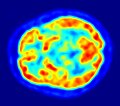

-

PET-Hirnaufnahme (axiales Schnittbild)